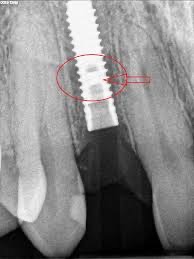

5️⃣ 植體周圍炎(需要特別注意)

這就是「植牙的牙周病」。

• X 光看到骨頭變少

越早發現越好,避免骨頭持續流失。

6️⃣ 植體鬆動(少見但最嚴重)

若植體本身與骨頭結合後受到過度咬力或感染,可能導致植體本體鬆動、斷裂。

這種情況通常需要重新評估、感染控制、甚至重新植牙。